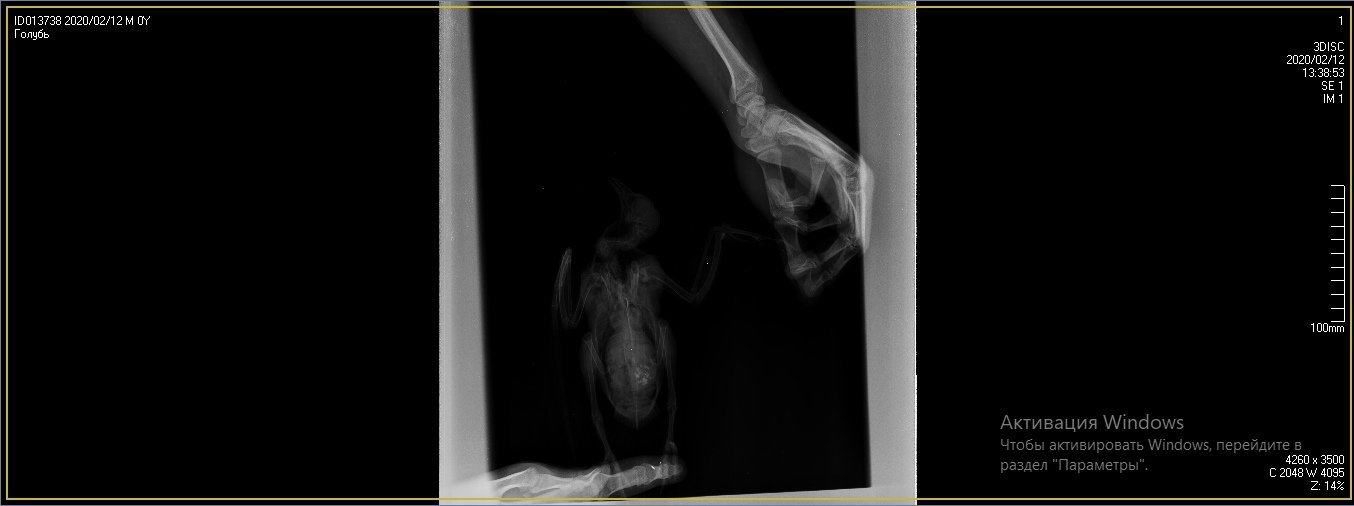

Duch Опубликовано 30 марта, 2020 #1 Опубликовано 30 марта, 2020 Здравствуйте! Приютился у нашего офиса, примерно 2 месяца назад, голубь и никак не улетал. Сделали вывод, что проблемы с крылом, т.к. левое он странно прижимал к себе. Положили в коробку, налили воды, насыпали гречи. Отогрелся спустя неделю, но крыло так и прижимал к себе. Предположили перелом крыла. Отвезли к орнитологу, сделали снимок (прикрепили к топику). Общий осмотр весьма позитивен, на снимке перелома нет. Выписали уколы витаминов и обезболивающих. Прокололи курс недели 2 назад - без изменений. На данный момент крыло так и прижимает к себе, огрызается, когда ему сыпят корм или доливают воды. Иногда клюёт и бьёт крылом, но только правым. Пока ждём выхода орнитолога из очередного отпуска, стараемся за ним ухаживать. В прошлую пятницу насыпали ему корм и подлили воды в плошку. Приехал в субботу вечером, дабы проведать. В итоге, он за целый день ничего не съел и не пил. На мои касания никак не реагировал: вжался в себя и стоял напуганный. Взял на руки, дабы осмотреть, как из под него показалась муха/слепень и тут же скрылась. Погуглил - оказывается, это - кровососки. Купил в ветеринарном отделе ампулу с препаратом, которую следовало разбавить 1,6л воды. Опрыскал её под крыльями, напоил водой из шприца и оставил так на день. Судя по корму, начал немного есть и пить. Кормплю гречкой, рисом и разваренным пшеном из шприца. Но сегодня обратил внимание, что он, когда клюёт сухой корм, как бы, промахивается и не может заглотить крупинку - гречка отскакивает в сторону и пытается еще раз захватить другую, но результат тот же. При всем при это, он четко видит мою руку и реагирует на неё соответствующим образом, т.е. слепоты нет Очень рассчитываю на вашу помощь! Ранее не имел опыта ухода за птицами

маленький принц Опубликовано 1 апреля, 2020 #5 Опубликовано 1 апреля, 2020 (изменено) а можно рентген более крупный а не мелкий? у Вас на этой мелкой картинке трудно разглядеть подробности ВНОВЬ ЛЕТАТЬ и Здоровья Вашему голубю! чтобы узнавать новые ответы в Вашей теме нажмите пожалуйста наверху Вашей темы "подписаться" Изменено 1 апреля, 2020 пользователем маленький принц

Duch Опубликовано 1 апреля, 2020 Автор #6 Опубликовано 1 апреля, 2020 31.03.2020 в 01:36, Виктория М. сказал: Здравствуйте. Нужен точный вес голубя. Помет желательно на листе белой бумаги. Проверьте нет ли наростов во рту , а также неприятныого запаха (кислого, тухлого). Кормить; 1 столовая ложка с горочкой 2 раза в день. Помимо гречи добавьте перловую крупу ,чечевицу или колотый горошек, пшеницу, овес без шелухи. Рис лучше уберите его можно но совсем немного. С каким препаратом ампула была? Все что обнаружил врач и все его назначения нужно выложить сюда на сайт, чтобы понимать чем вы лечили птицу. Какие витамины кололи какой курс и тд. Чтобы голубь начал нормально клевать зерно, в человеческой аптеке купите ноотропил таб или пирацетам . В вет аптеке нужно приобрести Фоспренил. Мух кровососок если вдруг еще обнаружите хорошо в тазике с водой вылавливать. Сажаете птицу в тазик с теплой водой, чтобы только голова на поверхности была, придерживаете аккуратно и так мин 10 -15 сидите с ним они начнут всплывать. Ваша задача не дать им вылететь из воды - передавить. Какое крыло он прижимает если смотреть на ренген? Прикрепил назначение врача Во рту ничего подозрительного, как и в запахе. Может прозвучать неоднозначно, но он в вцелом, приятно пахнет) Ампула, которую разбавил в воде и опрыскивал 2 дня голубя под перья ( на тело) - "Дельцид" В воду окунали, правда держали минут 5. Ничего не всплыло и мы аккуратно его сушили феном, т.к. он сильно замёрз. Потом на форуме прочел, что насильное купание голубей недопустимо Глядя на рентген то, что раскрыто, т.е. правое. Делали снимок лёжа на спине, соответственно, по факту, это левое крыло

OFA Опубликовано 2 апреля, 2020 #25 Опубликовано 2 апреля, 2020 @Duch сама доктор смотрела рентген птицы? Что-то сказала? Нужно позвать нашего форумского доктора @Zosia посмотреть рентген. Может так разложена птица, но мне что-то кажется, что плечевой сустав не в порядке, но лучше пусть Зося посмотрит. Птица взрослая, клевать умеет, значит проблема или с жкт, или вертячка в такой форме.

маленький принц Опубликовано 2 апреля, 2020 #26 Опубликовано 2 апреля, 2020 @OFA рентген - в виде мелкой картинки просил автора залить рентген покрупнее

маленький принц Опубликовано 2 апреля, 2020 #30 Опубликовано 2 апреля, 2020 (изменено) @Duch вот рентген Вашего пациента Изменено 2 апреля, 2020 пользователем маленький принц

маленький принц Опубликовано 3 апреля, 2020 #33 Опубликовано 3 апреля, 2020 12 часов назад, Duch сказал: ну да, разве не его я прикрепил в прошлом сообщении? оно почему-то ужалось до мелких размеров если пойти по ссылке https://www.mybirds.ru/forums/uploads/monthly_2020_03/1SXcxYu_0rk.jpg.d7c82758490ddb04a65127b887286e57.jpg.28c0e1b9697a84b0cce71b1ee39e8254.jpg и открыть то видно что оно очень мелкое потому я скачав Ваш архив перезалил фото и увидев что оно ограничено по размерам дважды обрезав перезалил ещё раз